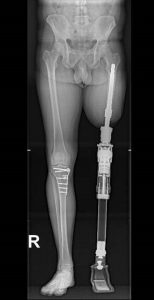

Prótesis tumorales (megaprótesis)

Diseñadas para sustituir grandes segmentos óseos resecados por tumores, generalmente en extremidades largas como fémur, húmero o tibia. Son altamente personalizadas.